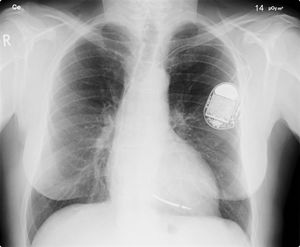

منظم ضربات القلب هو جهاز صغير مزود ببطارية صغيرة ووظيفته إرسال تنبيهات كهربائية للقلب بصورة منتظمة والتي بدورها تؤدي إلى انقباض القلب بصورة منتظمة وملائمة ليقوم بضخ الدم إلى جميع أجزاء الجسم.

1- مولد للتنبيه: هو عبارة عن علبة معدنية صغيرة الحجم بداخلها بطارية التشغيل بالإضافة إلى العديد من الدوائر الكهربائية المعقدة التي تعمل على مراقبة تعداد ضربات القلب وكذلك قوة التنبيه الكهربائي الموجه للقلب.

2- السلك الكهربائي: هو عبارة عن سلك مرن عازل يصل بين منظم القلب والبطين الأيمن، ويقوم بنقل التنبيهات الكهربائية من وإلى القلب.

إن معظم منظمات ضربات القلب تركب في الجزء الأعلى من الصدر من خلال عملية تستغرق حوالي ساعة واحدة تجرى تحت تأثير التخدير الموضعي فقط، حيث يقوم الطبيب المختص بعمل فتحة صغيرة في الجلد ومن ثم يتم إدخال المنظم تحت الجلد بعد إتمام عملية توصيل السلك الكهربائي في المكان الخاص به بالقلب عن طريق الأوردة ومن ثـم يتـم إغلاق هذه الفتحة بالخيوط الجراحية.